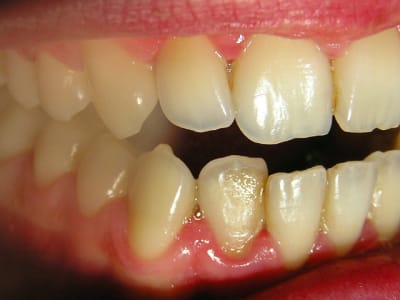

J'ai revu mon gendarme ce soir après 9 jours de flagyl + brosse Inava 15/100 trempée dans le paroex.

Il va beaucoup mieux: plus de douleurs bien sûr, presque pas de saignements, halitose disparue...

J'ai ressorti les photos prises initialement:

...Et les photos prises aujourd'hui, juste avant la séance de démonstration du contrôle de plaque.

Le but est de le revoir dans un mois pour déterminer sa motivation et son efficacité en matière de contrôle de plaque. Et pour voir comment la flore recolonise le terrain avant de lithotritier.